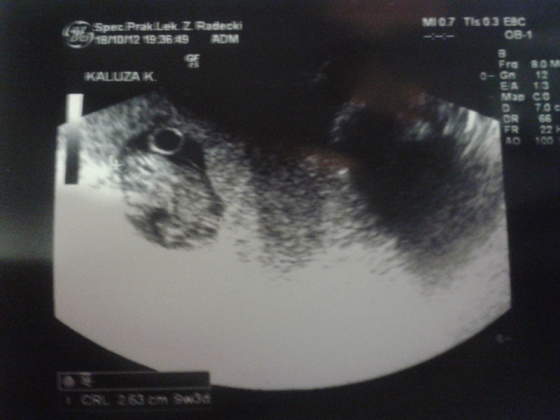

Dzidzius ma 2,36cm i serduszko 170 uderzen na min

) Z USG wychodzi 9w3d